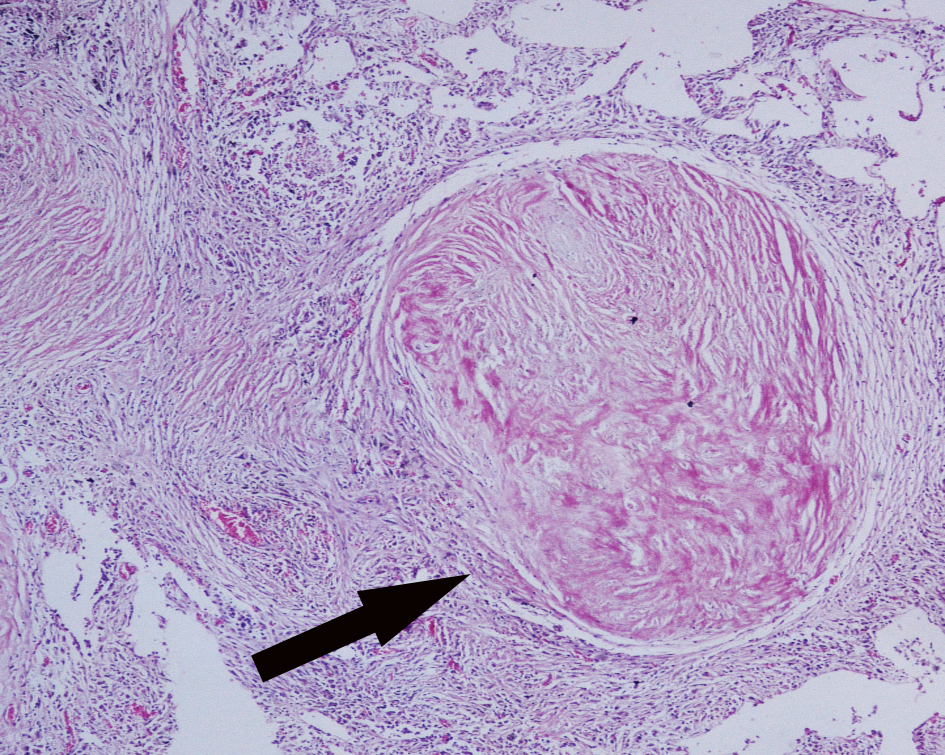

3.Arteriolosclerosis of kidney